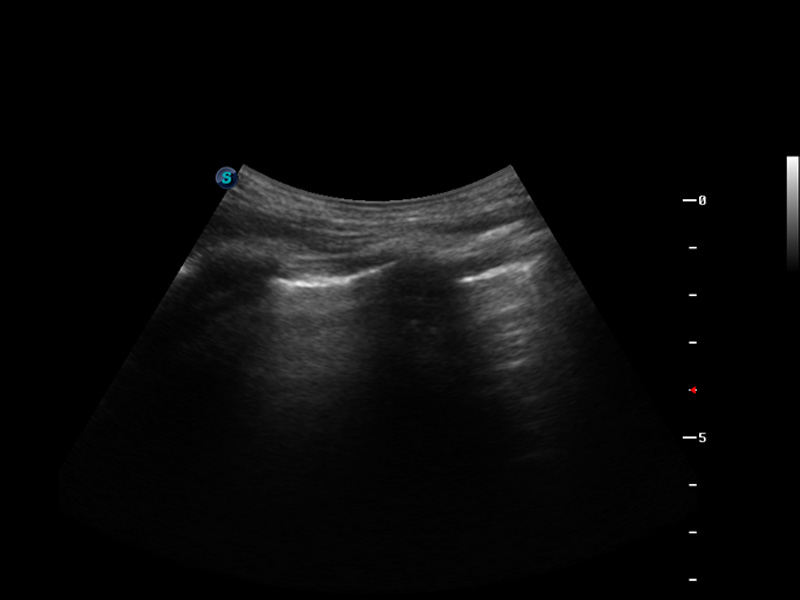

S9便携式彩色多普勒超声诊断仪是米兰官方网站研发的高端便携彩超设备,外观设计新颖、产品性能卓越。S9在便携超声领域采用了突破传统的触摸屏交互设计,并以先进的软件硬件技术和设计理念,为您带来清晰的图像质量、稳定的工作性能和便捷的操作体验。

脉冲反相谐波成像